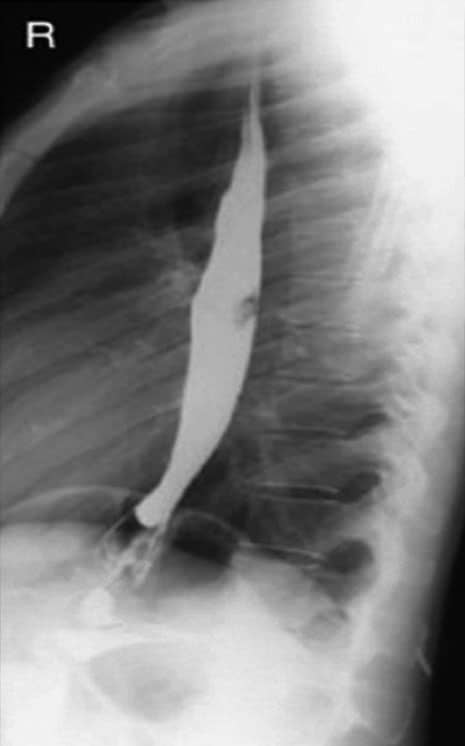

Incidência perfil de esôfago (esofagograma) – Trato gastrintestinal alto

Incidência perfil de esôfago em decúbito lateral direito.

Radiografias do esôfago contrastado em OAD (à esquerda) e em perfil (à direita).

Justificativa para realização do exame

Encontrar estreitamentos e corpos estranhos; anomalias anatômicas e neoplasias do esôfago são demonstradas nessa incidência radiológica.

Principais estruturas demonstradas

Toda extensão do esôfago em perfil, sem a sobreposição da coluna torácica e da área cardíaca.

Fatores técnicos e posicionamento

• DFF: 1m.

• Tamanho do filme/receptor de imagem e sentido: 30x40cm no sentido longitudinal.

• Técnica de referência: 6mAs e 110KV, na mesa ou no seriógrafo.

• RC: perpendicular no centro do filme ao nível de T6.

• Posição do paciente e da parte ou região do corpo: colocar os braços do paciente para cima, com os cotovelos fletidos e superpostos em decúbito lateral ou em ortostática. Preferível a posição deitada.

• Respiração: parar a respiração e expor durante e expiração.